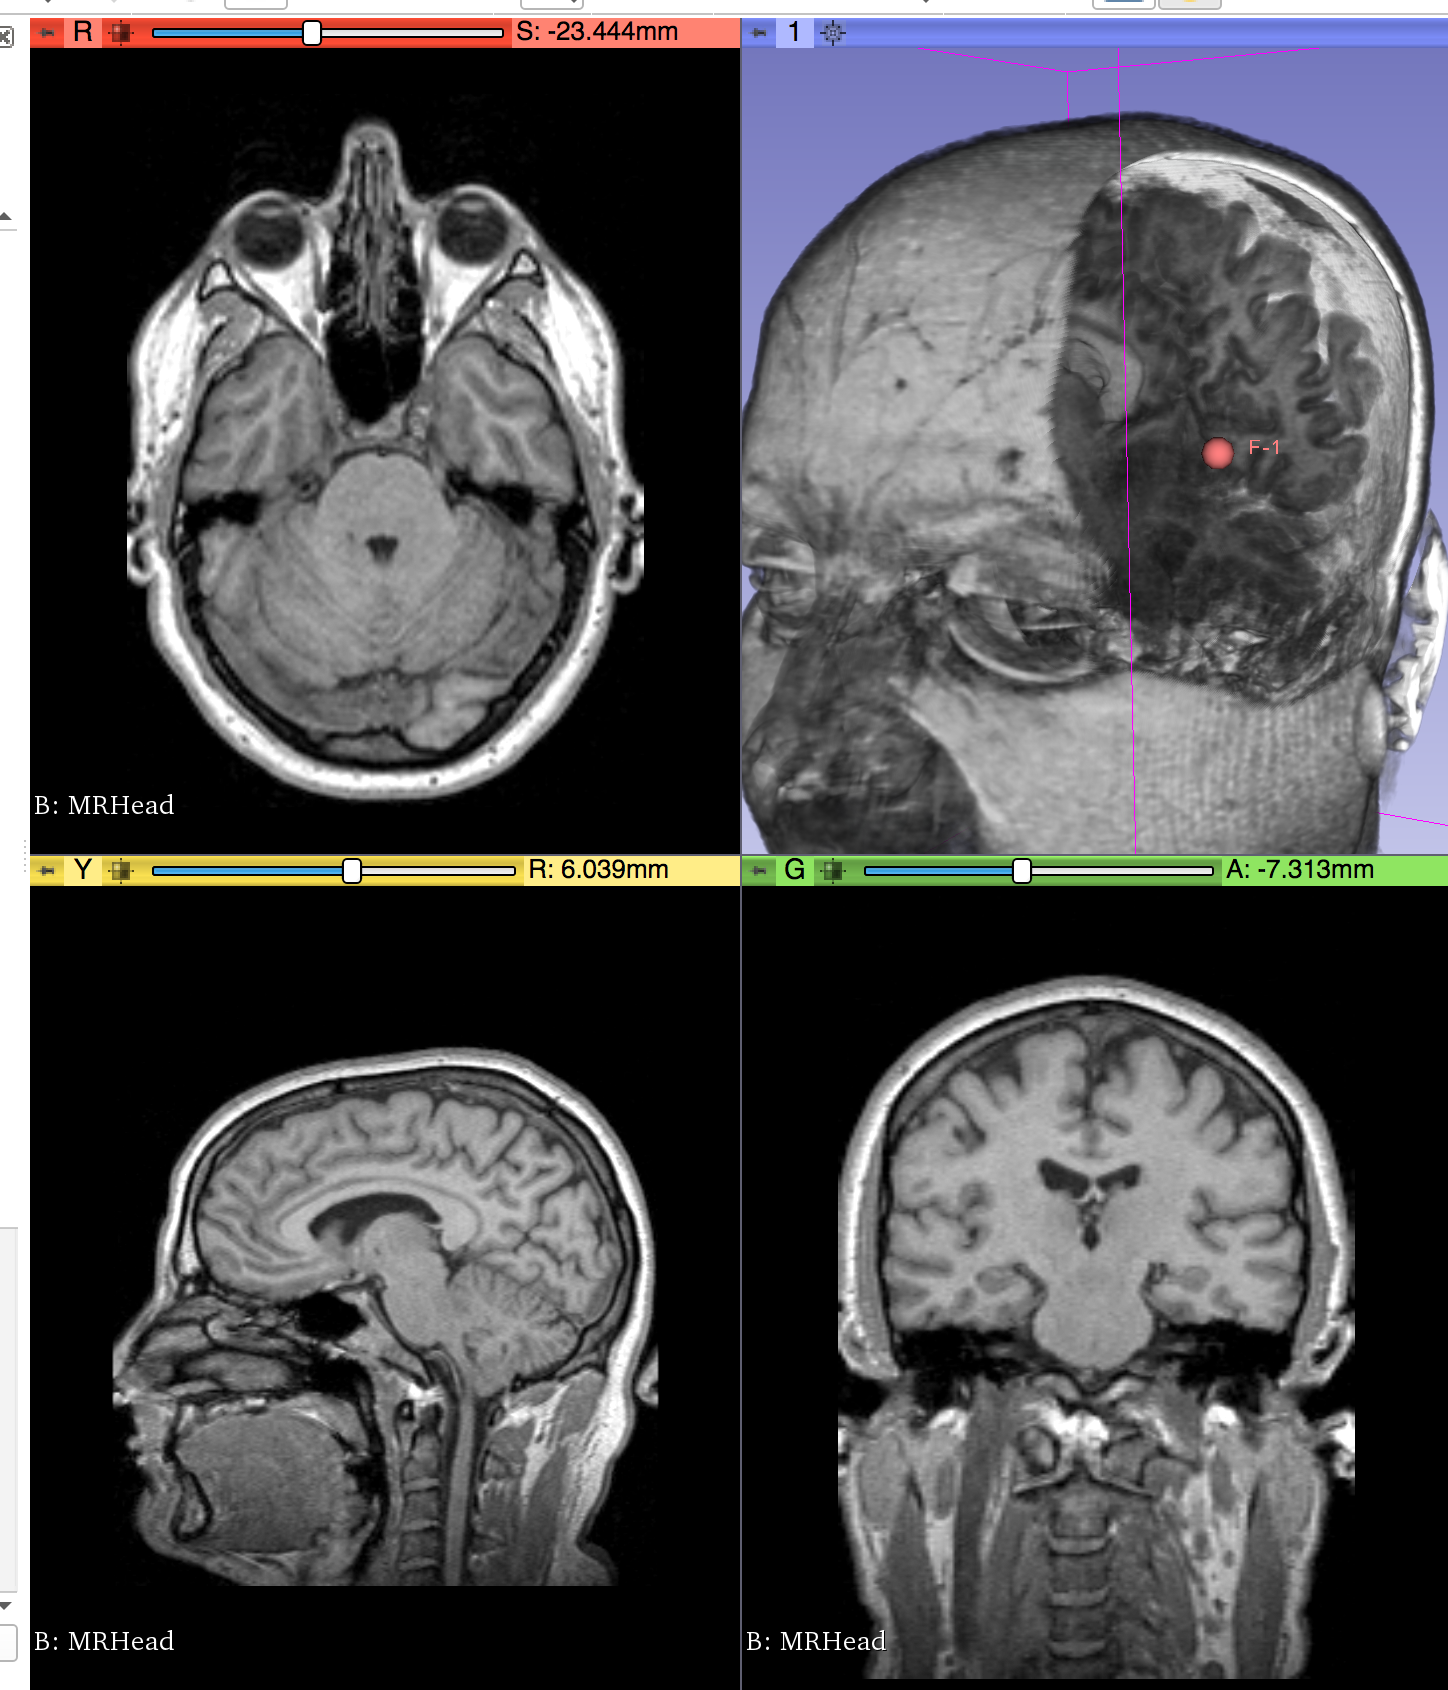

Illustrations

Philips 3D US Chroma-depth in PRISM Depth peeling in PRISM

Edge enhancement in PRISM Decluttering in PRISM Volume carving in PRISM